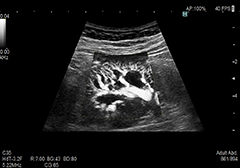

Detective Flow Imaging(DFI)

これまで描出困難であった低流速の血流を表示する新しいイメージング技術です。

独自のアルゴリズムで微細な血流をより高分解能に感度よく描出します。